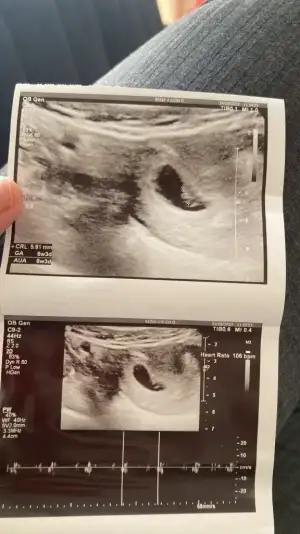

Benim kese nedense yuvarlak değil ince uzun belki ondan doktor düşük riski için iğne verdi bilmiyorum karından bakti bu şekilde önüme tutunce sol kolumun tarafında yani aslinda sol da ama bana göre sağda o zaman kız mı

Canım 6 haftalıkken ki ultrasonum benim de öyle dr bişey demedi. 7+6 da yuvarlak çıktı 😂 eğer karından ultrason ise sağa daha yakın gibi yani kız oluyor. Bak benim 6 haftalık keseme

Hshsshshsh 😂😂😂 şimdi benim karından ultrason sağda ya bebiş,aslında solda konumlu. Vajinal ultrasonda bakılsaydı solda çıkardı aynısını yansıttığı için. Çok basit aslında karından sağda ise kız solda ise erkek. Vajinal ultrason ise tam tersi😂 bu arada 6-8 haftalık ultrasona göre bakılıyor bu 9. Haftadan sonra benek hareket etmeye başlıyor yeri değişebiliyor .

kizlar dayanamadim benimkine de bakar misiniz :) vajinal ultrasondu ve 5+2 gunluktu.bir gun once gelseydin icini goremezdim dedi dr